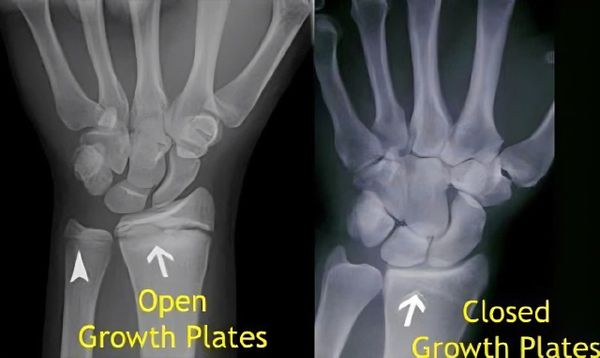

Hormone tăng trưởng (GH) có tác dụng mạnh mẽ nhất đến phát triển chiều cao trong giai đoạn tuổi dậy thì, khi các sụn tăng trưởng ở đầu xương dài còn hoạt động. Khi các sụn này cốt hóa (đóng lại) hoàn toàn, GH không còn khả năng kích thích tăng trưởng chiều cao nữa. Thông thường, cốt hóa sụn tăng trưởng hoàn toàn ở nữ giới, vào khoảng 16-18 tuổi và ở nam giới, vào khoảng 18-21 tuổi (xem hình: hình bên trái là chưa cốt hóa, còn sụn tăng trưởng, còn đáp ứng tốt với hormone tăng trưởng)